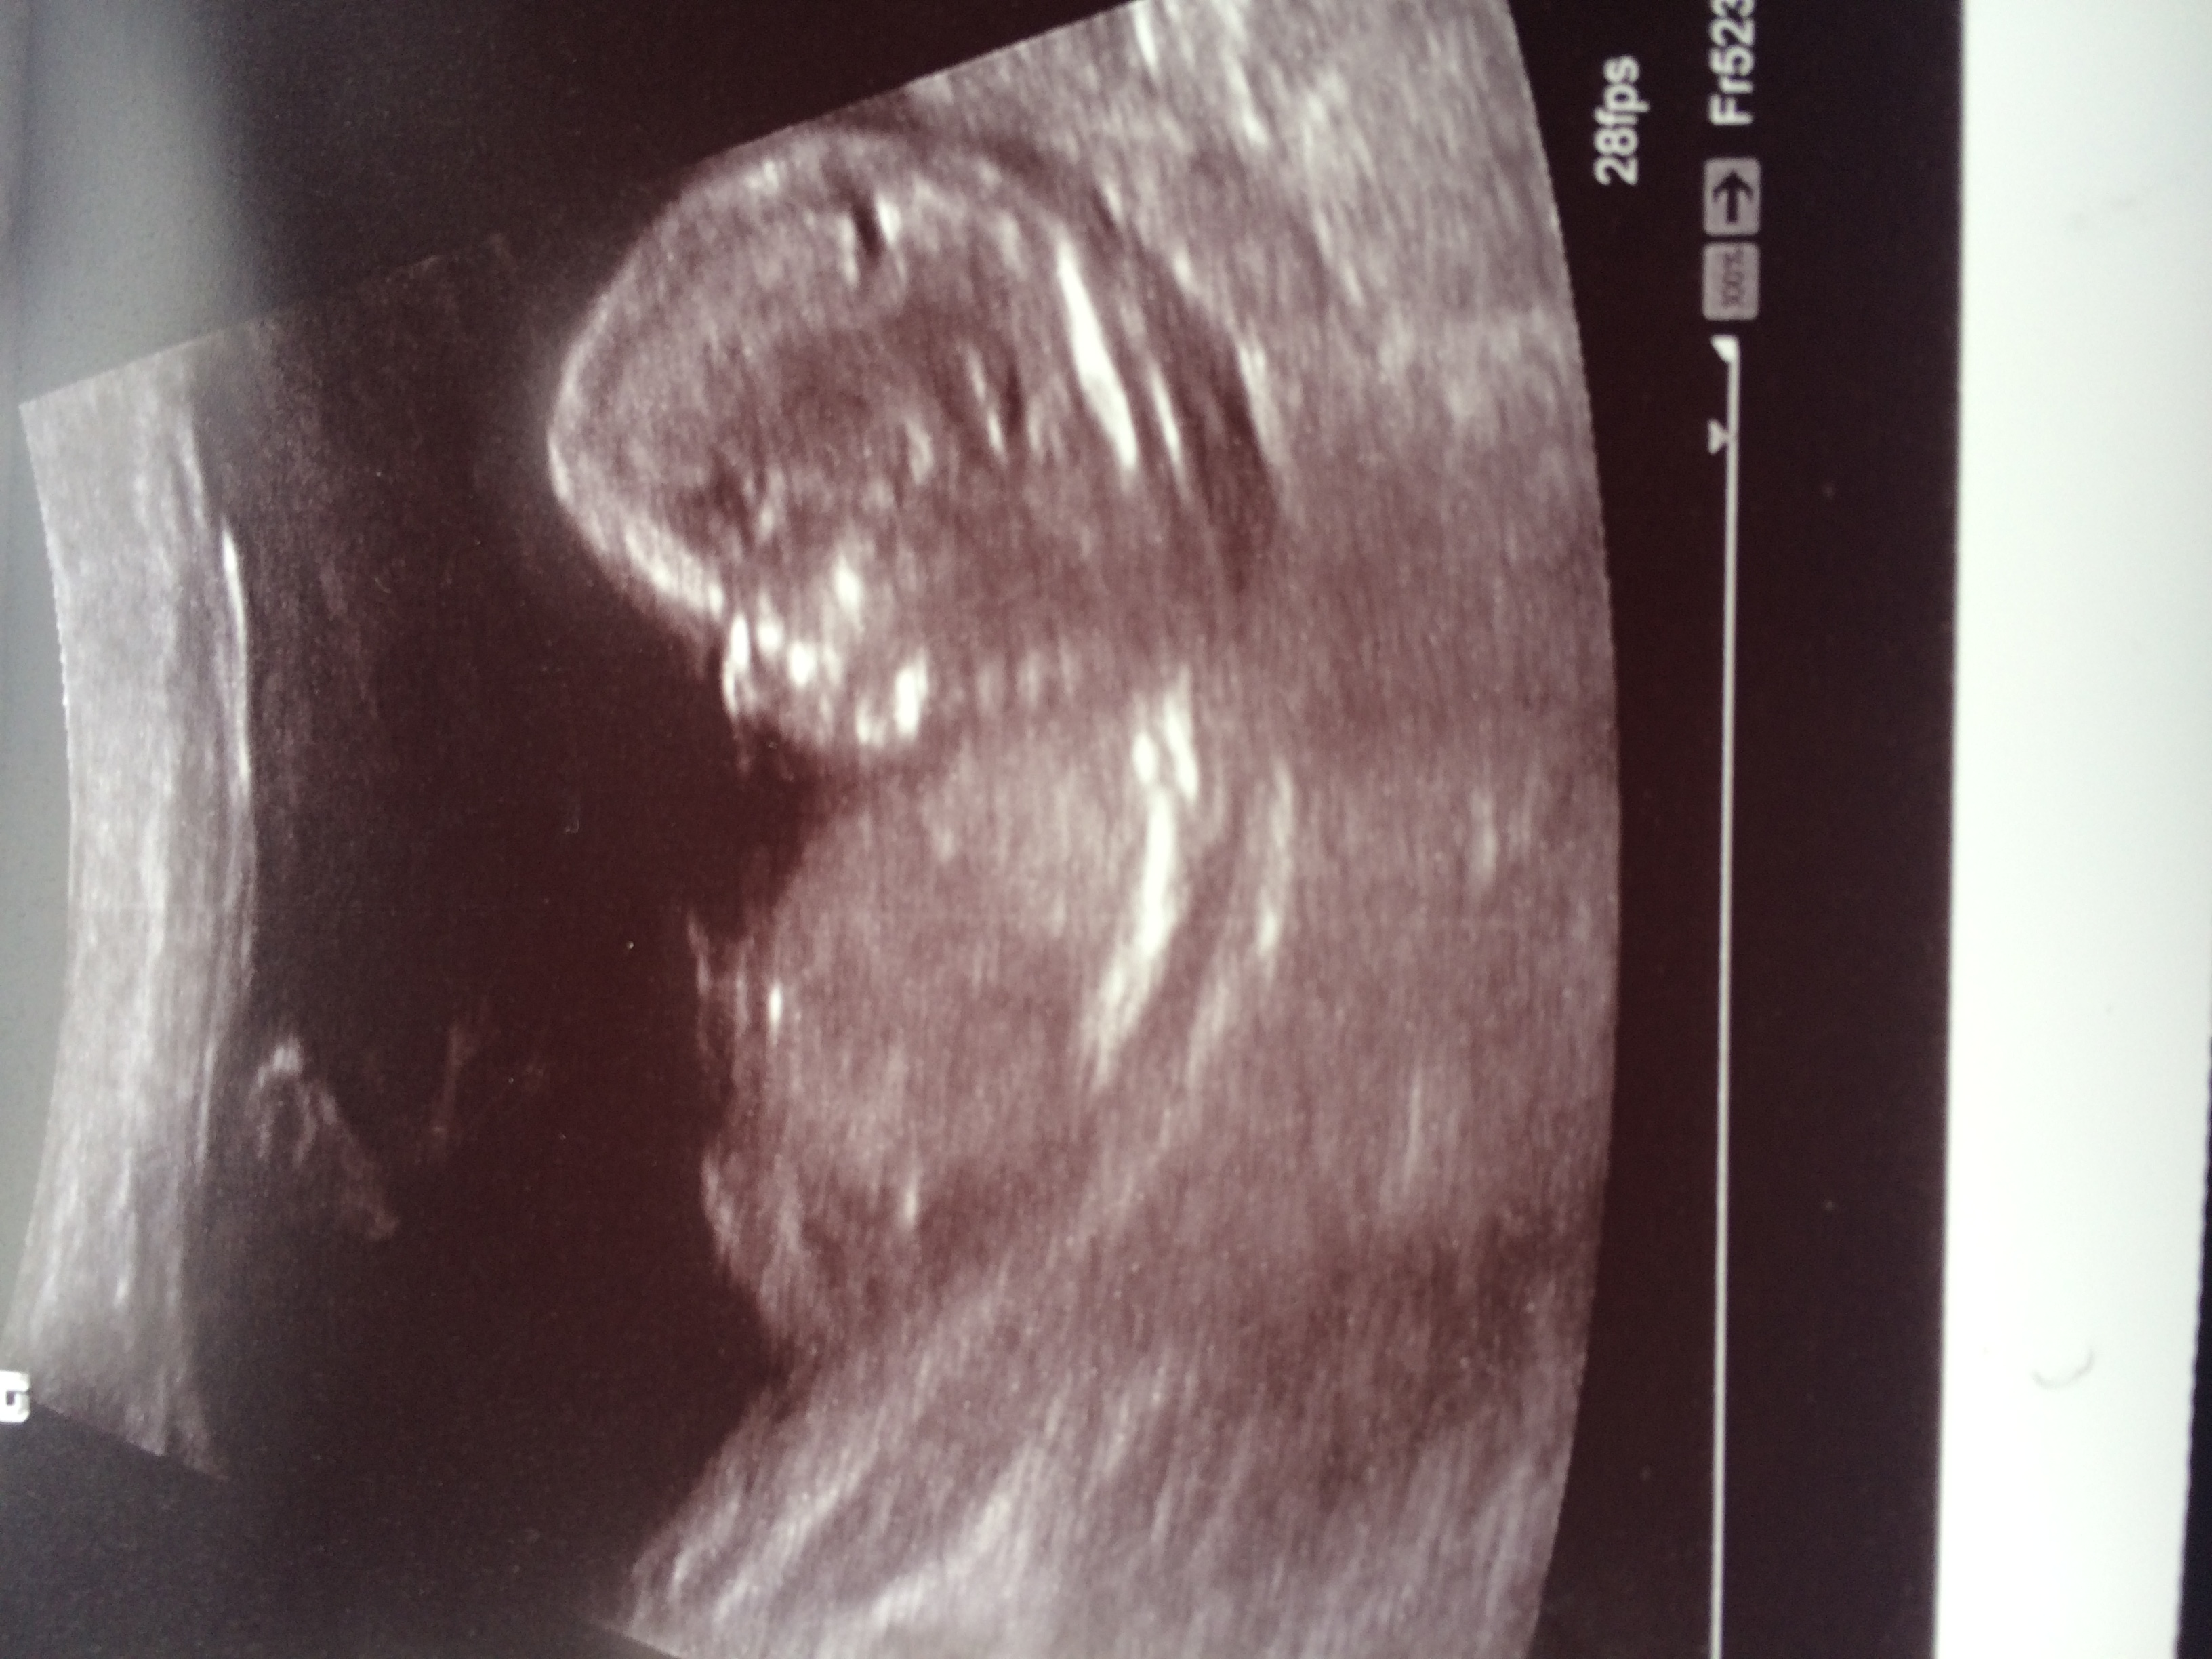

Hi, here is my 13w 1d ultrasound picture. Can anyone take a guess please? Attachment 27943Attachment 27944

It's flat nub, looks girly! Just my guess[emoji16]

I see nothing, but a cute foot in the first pic :)

I have absolutely no idea what to look for on my scan pictures lol I don't know where the nub is. I'm having a gender scan in 11 days. I already have 2 boys, hoping for a girl X

I'm having a gender scan on Friday, any last guesses?